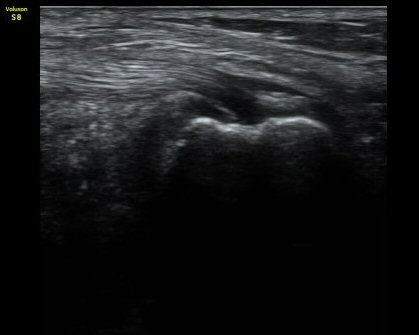

¹«¸­ ³»Ãø Á¾´Ü¸é°Ë»ç¿¡¼­ °üÀý°£°ÝÀÇ °¨¼Ò ¹× ¹Ý¿ùÆÇ¿¬°ñÀÇ ÅðÇ༺ º¯È­¿Í ¿ÜÃø À¸·Î µ¹Ãâ¿¡

ÀÇÇÑ ³»Ãø ÃøºÎÀδëÀÇ ½ÉÇÑ ¿ÜÃø µ¹Ãâ º¯ÇüÀ» º¸ÀÌ°í ³»Ãø ÃøºÎÀδë¿Í ¹Ý¿ùÆÇ¿¬°ñ »çÀÌ¿¡ ¹«¿¡ÄÚ

¼ö¾× Àú·ù°¡ °üÂûµÊ. °æ°ñ°ú ´ëÅð°ñÀÇ °ñ±ØÀÌ ¸Å¿ì ½ÉÇÑ »óÅÂÀÓ(±×¸² 1, 2).